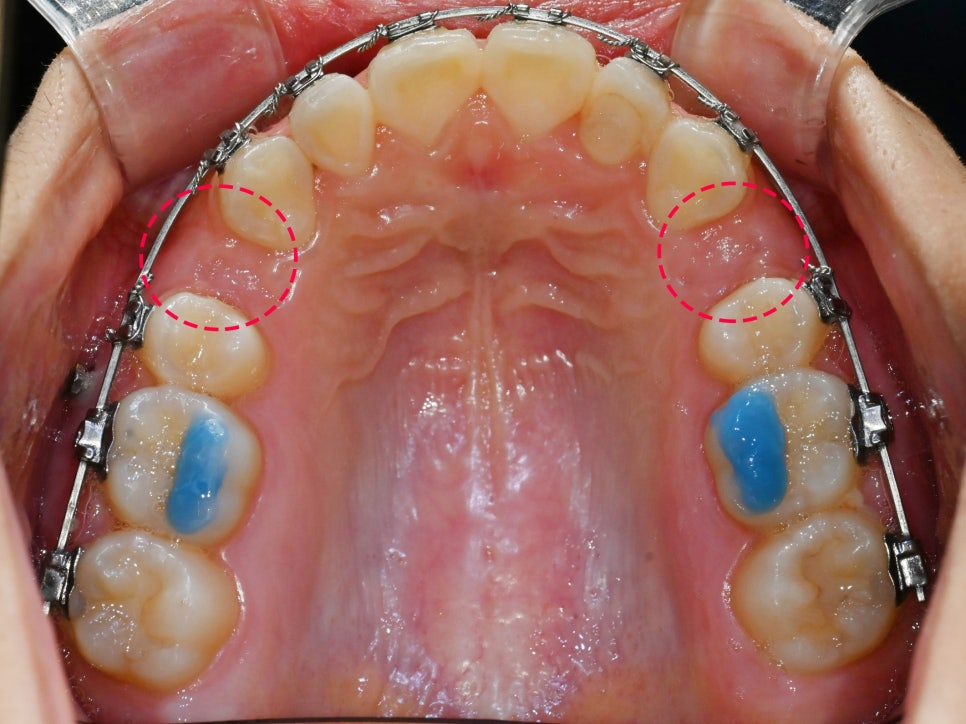

개선에 앞서 치열을 본래 위치로

정렬시키기 위해서는 이동시켜줘야 되는데요.

이동에 필요한 공간은 주로 소구치 발치로 형성합니다.

교정 발치의 경우에는

양쪽 위아래에 있는 소구치 하나씩을 뽑아

이동을 돕곤 합니다.

그런데 여기 사진을 보면 알 수 있듯이

양쪽 상악 소구치를 하나씩만 뽑는

‘편악발치’를 시행했음을 볼 수 있습니다.

이처럼 한 쪽 이만 심하게 돌출이 되어있을 때

편악발치 방법을 이용해볼 수 있습니다.

편악 발치를 통해 위쪽의 14번과 24번을 뽑은 뒤,

치아를 이동시켜 조정하고 있는 모습을 볼 수 있습니다.

치료를 시작한 지 얼마 안 된 시점에서는

아직 유격이 존재해 다소 빈 느낌이 들지만,

서서히 치열 개선이 되면서 유격된 부분은 폐쇄됩니다.